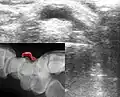

Ультразвуковое и рентгенографическое (на врезке) изображения гигромы запястья -